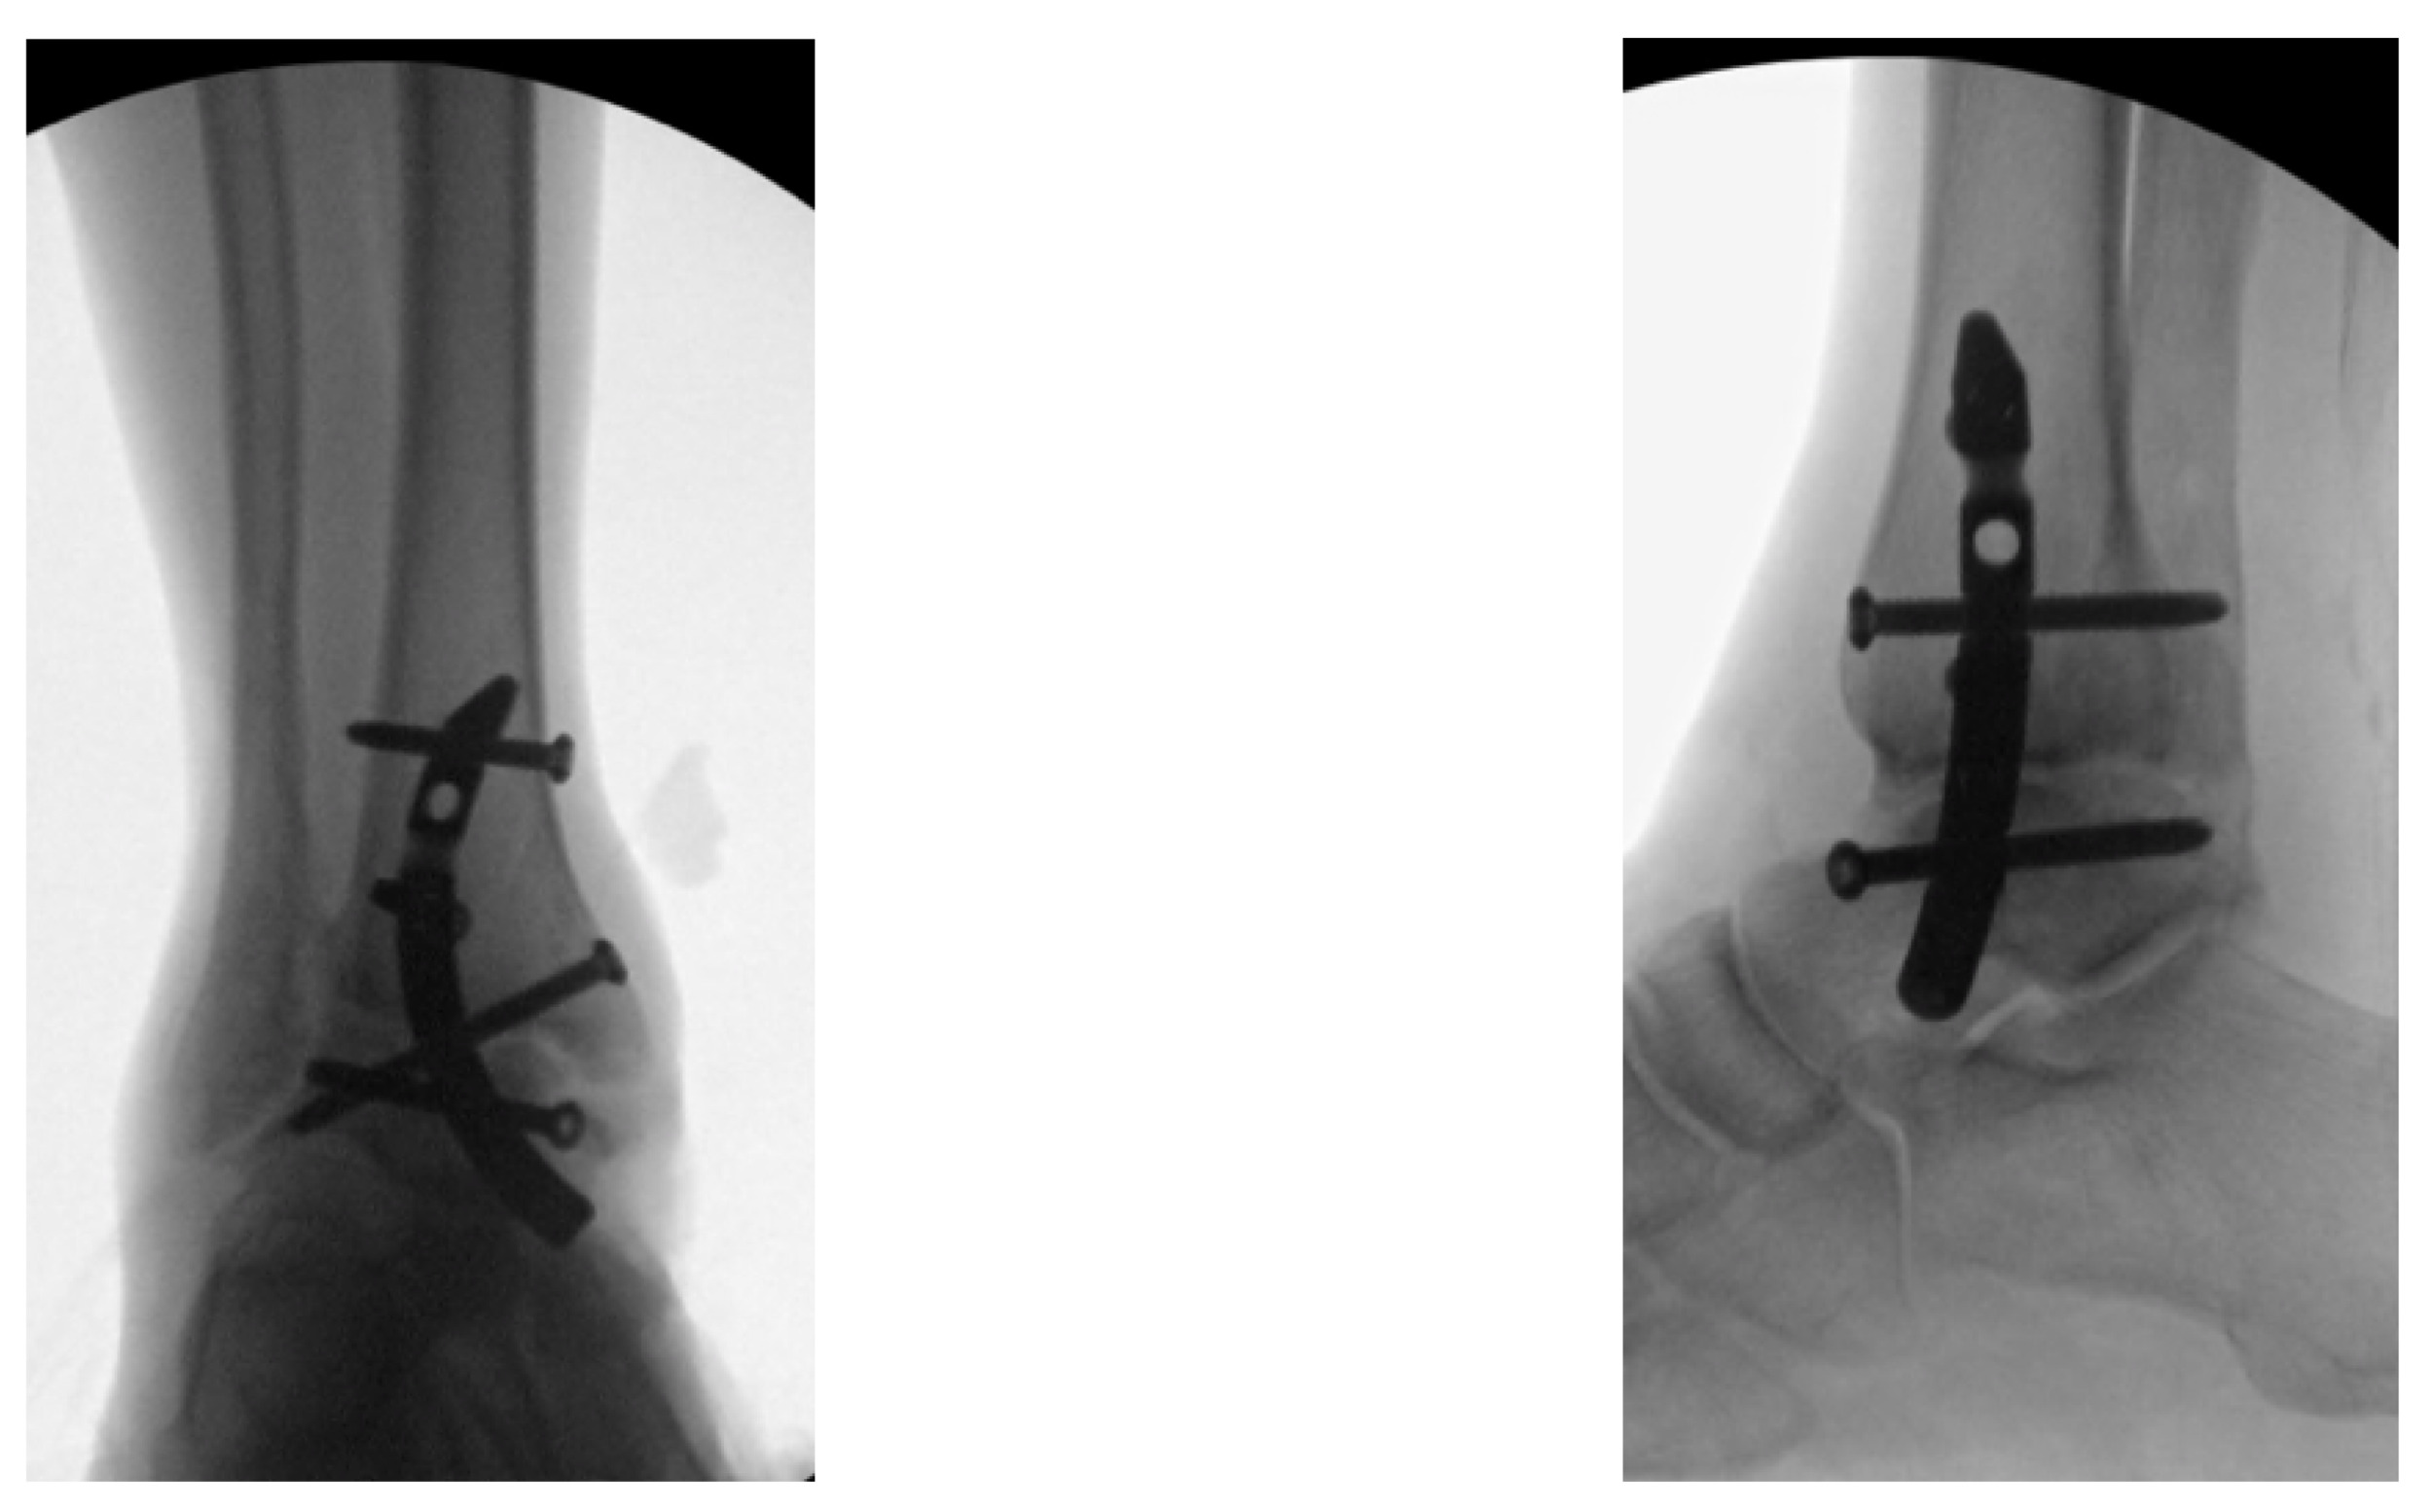

Provisional fixation: Achieved utilizing 2.4 mm pins posteromedially and anterolaterally with the joint in the optimal position (neutral flexion, 0º-5º valgus, and 5º-10º external rotation) [Figures 1A-B].

The drill guide and compression sleeve are removed, the nail cap is placed, and the wound is closed in layers [Figures 6A and 6B].

Examples of postoperative images of the Shotel Nail are included in [Figures 7A-C].